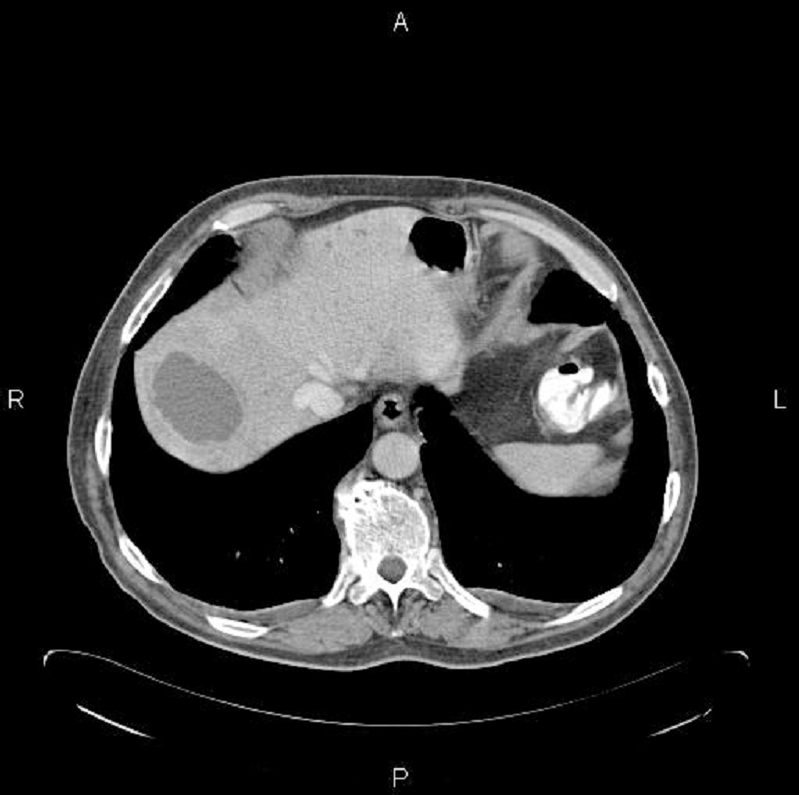

A 72-year-old gentleman presented with a three week history of fatigue, night sweats and rigors. He was initially assessed by his General Practitioner who started a course of penicillin but, unfortunately, on completion of the antibiotics the rigors recurred. There was no associated cough, diarrhoea, weight loss, abdominal pain, dysuria or contact with any tuberculosis patients. Past medical history was remarkable only for nasal polyps and hypertension, for which he was treated with ramipril and bendroflumethiazide. The patient reported alcoholic intake of 16 units per week, with no history of intravenous drug abuse or of receiving any blood or blood product transfusions. The patient was immunocompetent and not diabetic or on steroid treatment. Examination was unremarkable but initial blood tests revealed an elevated ALP 421 IU/L (normal range 20-130iu/L), CRP 180 mg/L (Normal range <5 mg/L) and white cell count 16.1x109/L (normal range 4.0-11.0x109/L) with a neutrophilia of 15.40 x109/L (normal range 1.70-7.50 x109/L). Ultrasound scanning of the abdomen revealed three echo poor areas in the liver, the largest of which was 3.8 cm x 4.2 cm. This was thought to represent either an abscess or a metastatic deposit. Blood culture did not yield any results, but the patient was given a stat dose of 320 mg of gentamicin and 1.2 gm intra-venous co-amoxiclav three times a day. A CT scan of the abdomen was performed which revealed a hepatic abscess of 3.8 x 4.2 cm (Figure 1), which was drained percutaneously under ultrasound guidance. This aspirate was cultured and grew F. nucleatum noted to be sensitive to penicillin and metronidazole. Follow-up CT scan was performed, which showed marked resolution of the hepatic abscess.

Click below to enlarge

Figure 1: CT scan showing liver abscess, which was drained percutaneously.